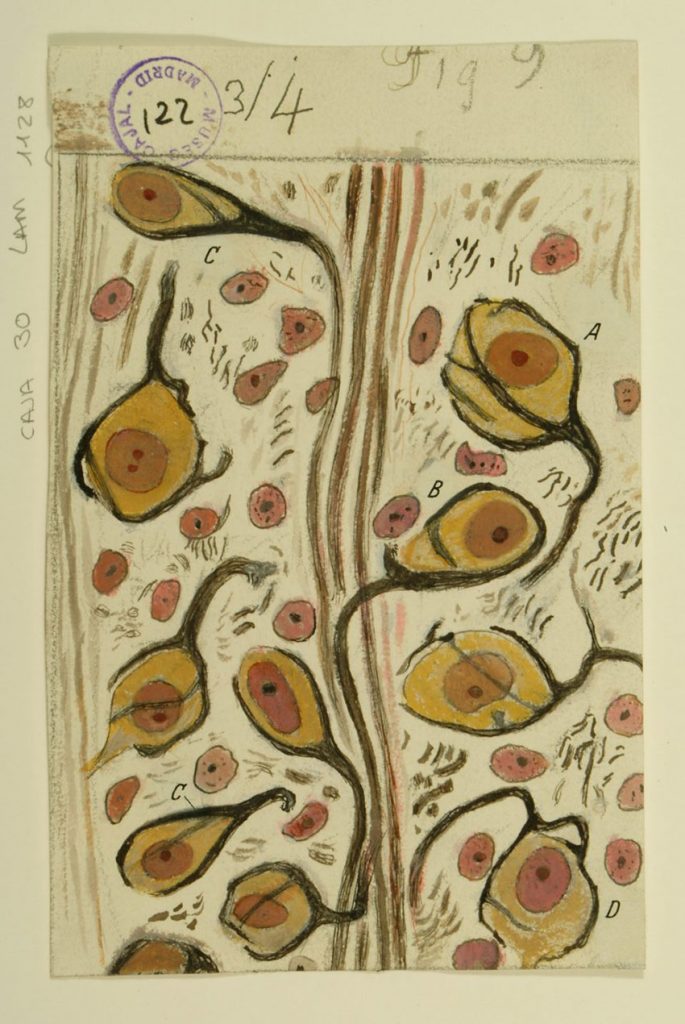

Santiago Ramón y Cajal

Grey Art Gallery

New York University

Greenwich Village, Manhattan

Tuesday – Saturday

January 9 – March 31, 2018